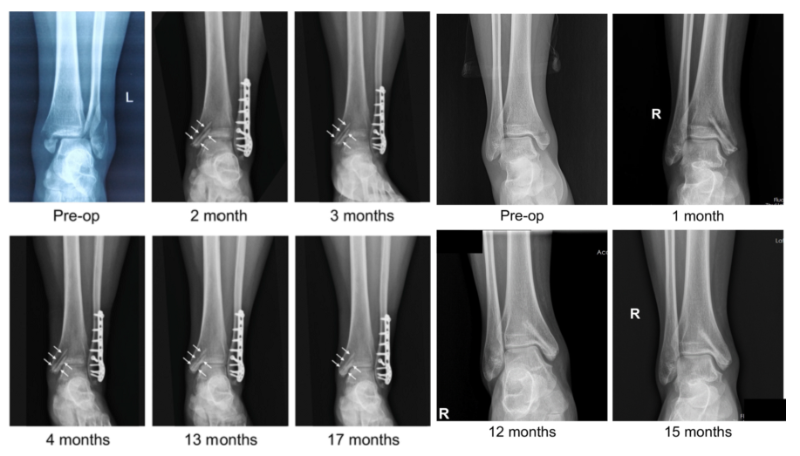

近日,國際骨科臨床轉化期刊《Journal of Orthopaedic Translation》在線發表了由上海交大戴尅戎院士、郝永強教授團隊和丁文江院士、袁廣銀教授團隊合作發表的可降解鎂合金骨釘1-2年的臨床試驗觀察結果,所有患者術后內踝骨折愈合,功能恢復。研究證實了可降解鎂合金螺釘治療內踝骨折的臨床療效及其生物安全性,為全降解鎂合金植入物等高端醫療器械進一步的臨床推廣應用奠定了堅實基礎,相關成果以“Effectiveness and safety of biodegradable Mg-Nd-Zn-Zr alloy screws for the treatment of medial malleolar fractures”為題在線發表于Journal of Orthopaedic Translation,27 (2021) 96–100。這是國內首個可降解醫用鎂合金臨床試驗的公開報道,也是國際首款含有功能涂層的可降解鎂合金骨釘的臨床試驗結果的公開報道,具有里程碑意義。